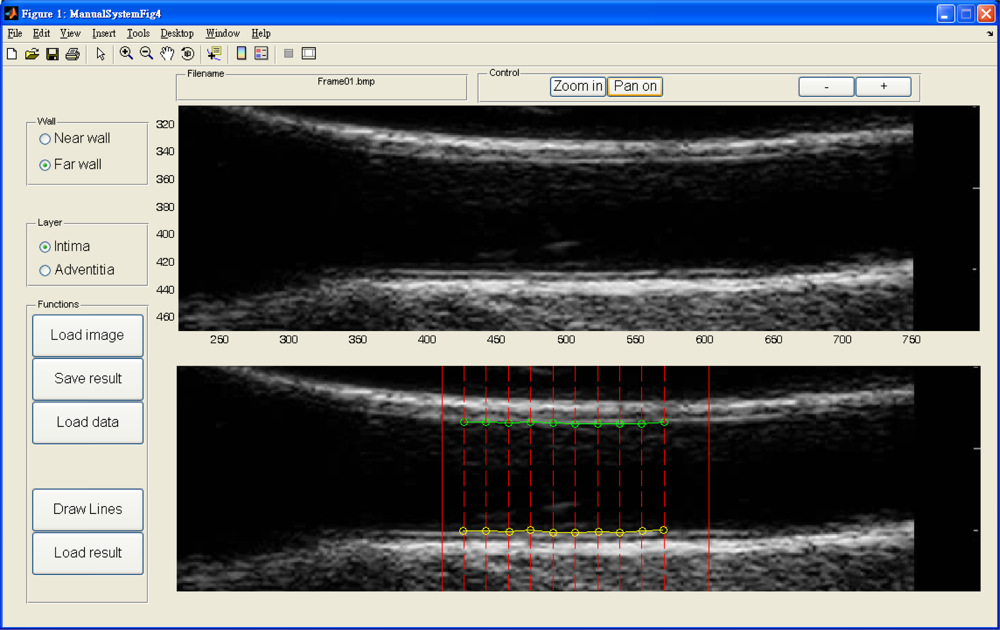

A typical B-mode image is shown in Figure 1. There are plaques on both near and far walls. On the contrary, a typical CCA image without plaque having thin and thick IMT is shown in Figures 2 and 3, respectively. Outlining the boundaries of intima and adventitia is not easy, especially on the near wall. Some features have been studied in previous studies [7,11], in which the most frequently used feature is the gradient of gray-values. From our previous studies [7,14,17], it is found that MacLeod operator combined with some specific enhancement filters are very suitable for feature extraction in intima and adventitia detections.

The dynamic B-mode sonographic sequences are recorded and converted to a series of static images and saved in BMP format. A graphic user interface (GUI) is designed for the user to select a region of interest (ROI) for the following automatic analysis. The selected ROI is a rectangular area which is large enough to cover the possible area during a complete systolic and diastolic cycle. Similarly, when the IMT is analyzed, the rectangular area covers only the intima, adventitia, and part of artery lumen area. However, since the IMT does not change too much during the heart cycle, the rectangular area for IMT measurement is much smaller than the one for lumen diameter measurement. After the ROI is selected, the following analysis and measurement processes are fully automatic.

An accuracy study is an assessment of the reliability of a system. In order to compare results made by the proposed automated system, we developed software for manual drawings. The manual drawings were performed by well-trained radiology technicians and then confirmed and modified by a medical physician. Four layers were drawn, i.e., intima and adventitia of both near and far walls. The linear interpolation is applied to fill out points between two points in manual drawings.

Figure 14 depicts our manual drawing GUI. The solid lines denote the boundary of the automated analysis. The dashed lines denote where the expert should give their judgment on the lumen-intima interface. Manual drawing involves a tremendous amount of human work. Although we are not able to provide many manual drawings for comparison, however, the automated results were controlled visually by experts and all results are similar to those shown in Tables 1 and 2. The system is built on the Matlab platform. Some kernel functions are written in C language in order to reduce the computation time.